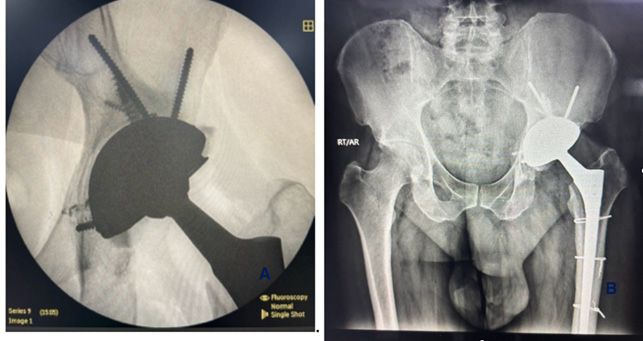

The revision was performed using the previous posterior (Southern Moore’s) incision. Upon exposure of the joint, blackish discoloration of the periarticular soft tissues was observed, suggestive of metallosis. After femoral head dislocation and removal, the cobalt-chromium liner was found to be mal-seated within the titanium acetabular shell and not locked into place. There was extensive metallosis at the liner-shell interface, resembling classic backside wear, and signs of screw head erosion were evident (Figure 2). One of the screw heads had a part protruding outside the shell. Discolored and necrotic tissue samples were sent for histopathological evaluation.

Figure 2: Intraoperative images (A) Arrow showing black stained periarticular tissues, including the tensor fascia Lata, tendinous insertions, and capsule. (B) Arrow showing acetabular shell with areas of metallosis (C). Arrows showing excised black colored necrotic tissue with prominent screw heads and screw head erosion inside the titanium shell (D). Arrow showing screw head erosion (E). Arrow showing corrosion behind the titanium cup.

Reconstruction was carried out using a press-fit TMARS™ (Trabecular Metal Acetabular Revision System) (Zimmer Biomet Warsaw, Indiana, USA) shell secured with multiple screws, including a kickstand screw for added stability. A cemented Evolutis Dual Mobility polyethylene liner was implanted, and femoral reconstruction was performed using a 14 mm × 225 mm Wagner revision stem (Zimmer Biomet Warsaw, Indiana, USA). Following final reduction, the construct demonstrated excellent intraoperative stability, a full impingement-free range of motion, and restoration of limb length (Figure 3).

Figure 3: Post-operative plain radiograph (anteroposterior view) of the right hip showing an acetabular cup with a screw and a well-fixed uncemented femoral stem. (A) fluoroscopic image intra-operative (B) immediate post-operative X-ray.